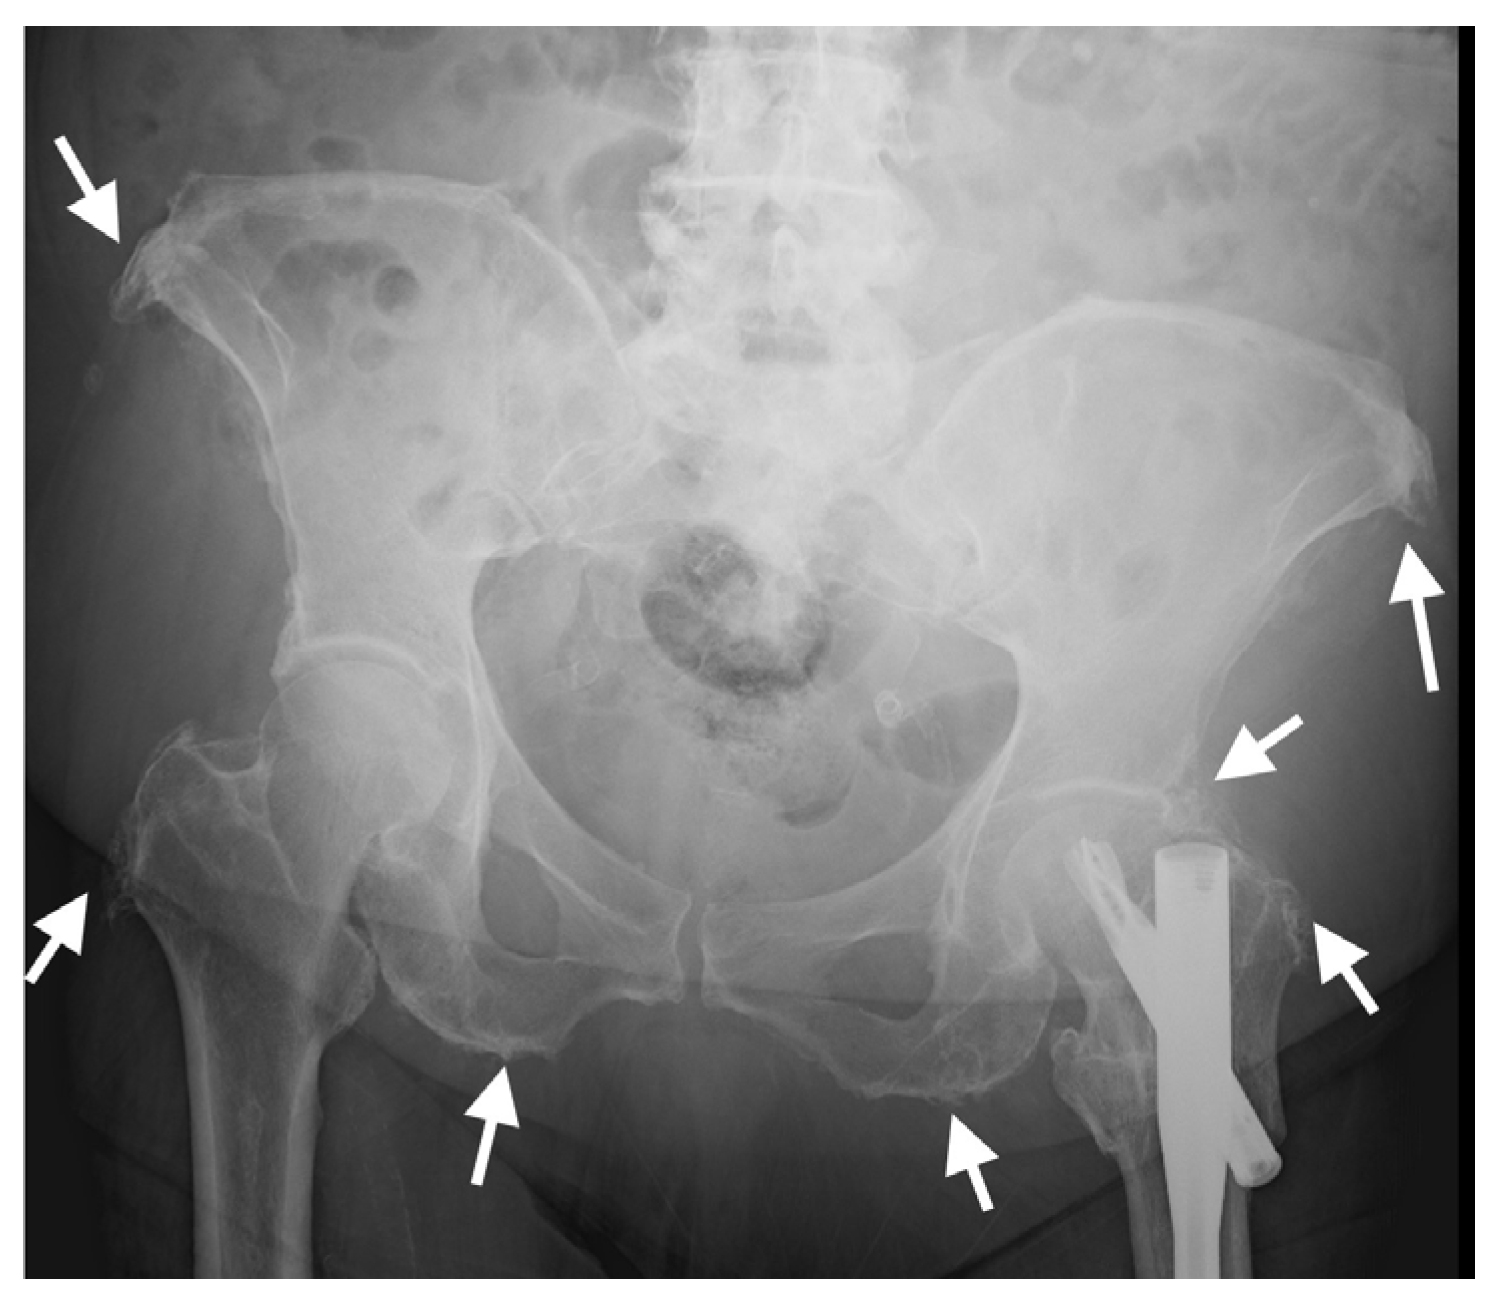

Enthesopathy of the sacrotuberous and iliolumbar pelvic ligaments and insertional enthesopathy of tendons such as the iliopsoas, as seen on pelvic AP radiographs (Figure 8), have been shown to be a good indicator of the presence of radiographic spinal DISH [74,75]. A similar association was described for CT examinations of the pelvis, in which enthesopathy was significantly more prominent in subjects with DISH compared with controls for all entheses evaluated (anterior superior iliac spine (ASIS), pubis, ischial tuberosity, greater trochanter), and enthesopathy at the ASIS and greater trochanter significantly distinguished DISH patients from controls [3].

Figure 8.

AP radiograph of the pelvis of an 82-year-old female with thoracic DISH (not shown). Characteristic whiskering of the anterior superior iliac spine and ischial tuberosities (arrows) is present on both sides, resulting from enthesopathy in these regions.